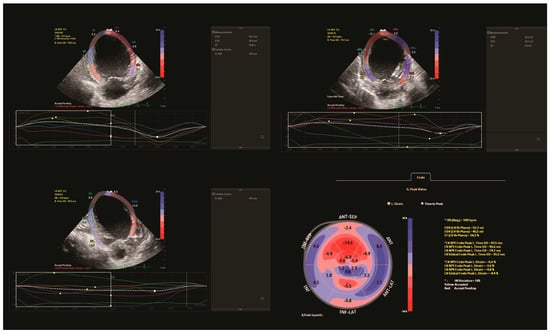

| Admission | Postoperative (Day 15 Postop) | Infection Time (Day 23 Postop) | Discharge (Day 70 Postop) | |

|---|---|---|---|---|

| LV EF (%) | 18 | 25 | 20 | 30.8 |

| LVEDD (mm) | 44 (z score = 7.29) | 41 | 40 | 35 (z score = 5) |

| LVOT VTI (m/s) | 1.1 | 0.9 | 0.8 | 1 |

| GLS | −4 | −8 | −5 | −7.9 |

| NT-proBNP (pg/mL) | 60,477 | 15,000 | - | 7226.4 |

| Troponin T (pg/mL) | 138 | - | - | 23 |